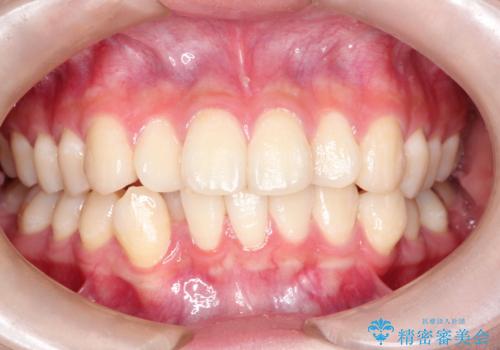

インビザラインによる矯正治療(非抜歯) 前歯の捻れとガタつきの改善

- 上下の前歯に捻れ(捻転)とガタつき(叢生)が見られます。

上の2番目の前歯の捻れに関しては、元々歯の大きさが小さい歯であるため、マウスピースにて力がかかりにくく、捻転の改善が一般的に難しくなりがちです。

下の犬歯に関しても捻れと傾き、ガタつきが大きく、歯根の長さも相まって移動の難易度が高くなりがちです。

インビザラインのそうした特色を踏まえた上で、それらをリカバーできるように治療方式の調整を十分に行い、治療を進めました。

マウスピース枚数 初回33枚 +追加22枚 +追加31枚

概ね2年で治療完了しました。

マウスピース矯正の特性として動かすのが難しい歯を含むケースでしたが、当院独自の工夫を随所に盛り込み、狙い通りの治療結果が得られました。